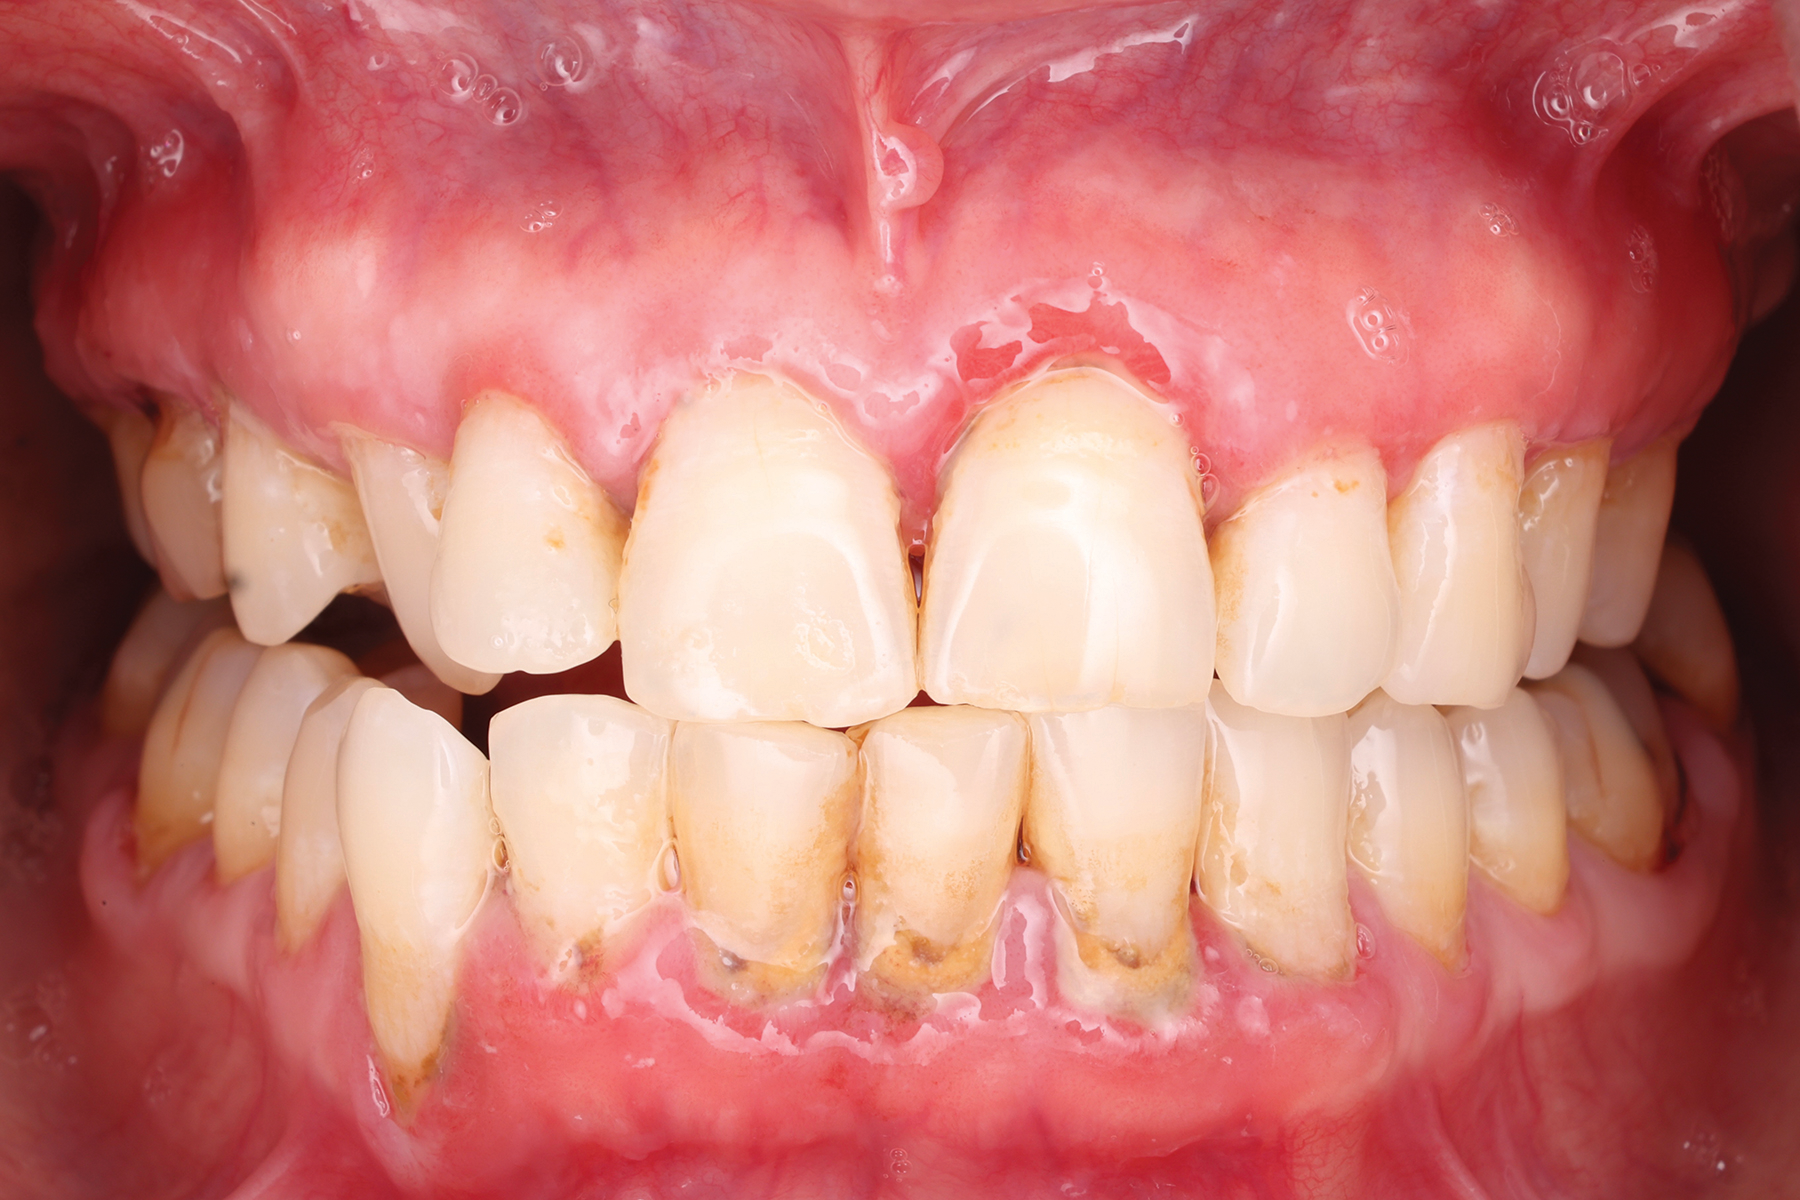

PV is a severe autoimmune disease caused by autoantibodies against desmosomes, leading to intraepithelial clefting and the formation of vesicles and bullae on the skin and mucosa (Figure 3). In approximately 70% of PV cases, the condition may be triggered by medications or vaccinations. PV mainly affects middle-aged adults, particularly those of Mediterranean, Ashkenazi Jewish, or South Asian descent, with a prevalence of about 1 in 5 million individuals. Serum autoantibodies are typically present in patients with skin involvement but less common in those with only oral manifestations.8 If untreated, PV can be fatal.2

Fig 3. Pemphigus vulgaris in a 51-year-old Asian Indian female patient. This patient presented with an established diagnosis of PV at dermatologic and genital mucosal sites. She was taking oral immunologic modifiers prescribed by a rheumatologist prior to her examination in the periodontology clinic. Upon presentation, the patient demonstrated multiple ulcerated lesions at gingival tissues. The anterior mandible was the most affected area with marginal ulcerations and fibrin clot present. The patient reported difficulty in delivery of oral hygiene and in oral nutrition.